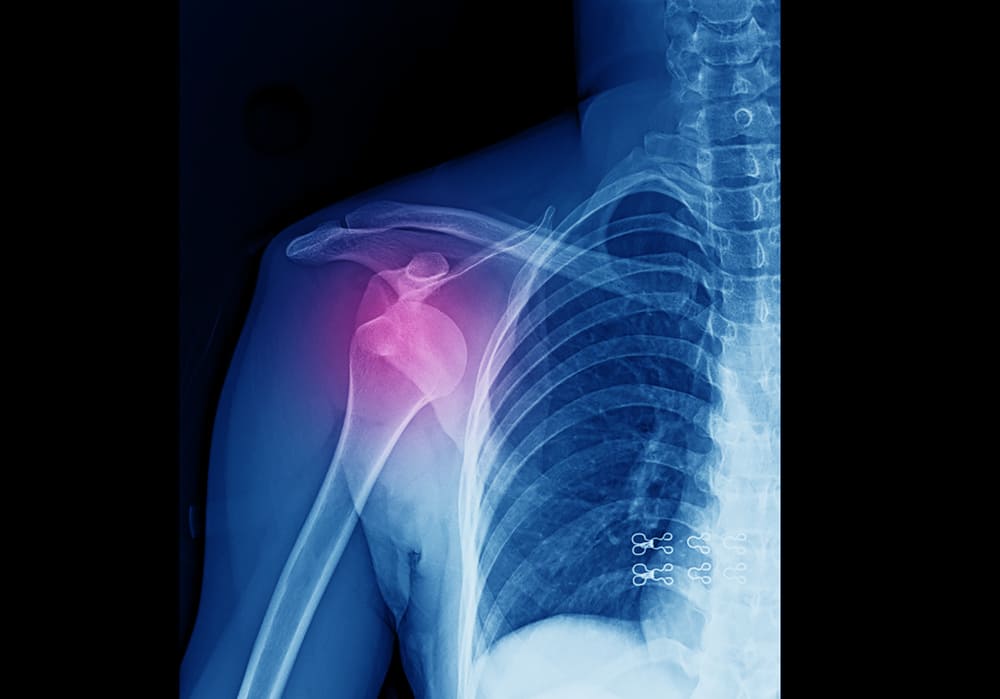

Скелетное вытяжение – это востребованный способ лечения разнообразных переломов. Данное хирургическоевмешательство позволяет устранить сместившиеся и деформированные костные отломки с использованием тяги. Скелетное вытяжение дает возможность преодолеть ретракцию и сокращение мышечных волокон, растянуть первичную костную мозоль. Операцию проводят в клинике.

• переломы диафиза бедра, плечевой, малой берцовой и большой берцовой костей;

• закрытый перелом таза, костных структур кисти, плеча, пяточной кости, плюсны;

• вывихи, переломы и их сочетание в шейной зоне позвоночного столба;

• неправильное срастание костных частей после прошлых травм плечевой или бедренной кости;